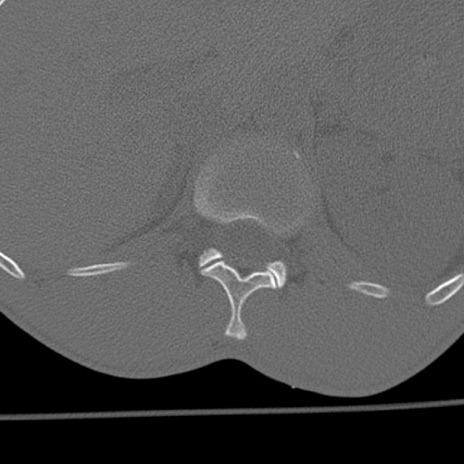

症例3 腰椎CT(横断像)

腰椎CT